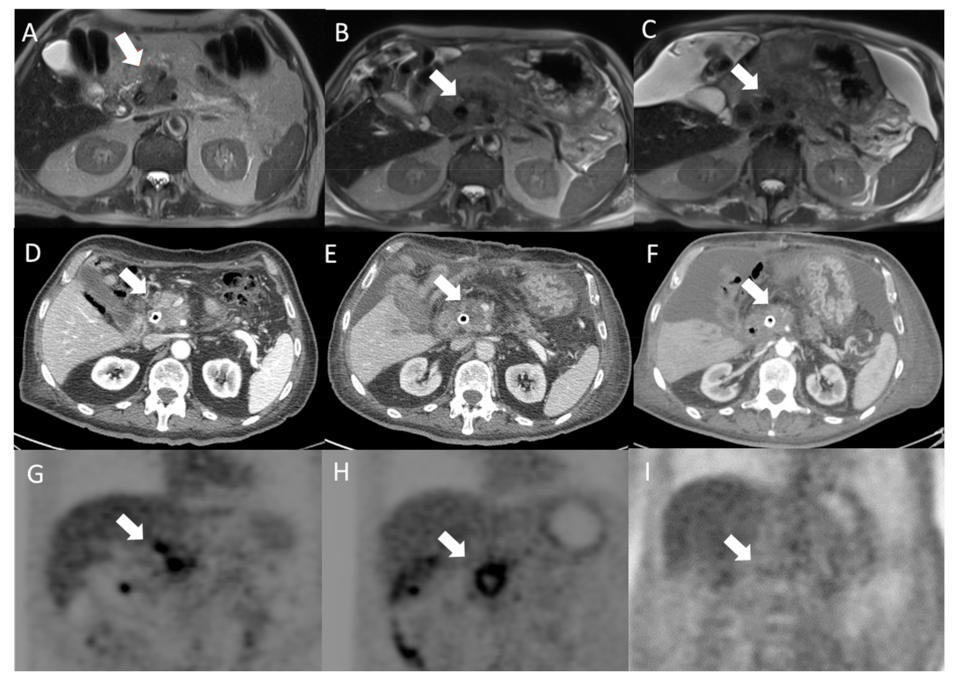

2.3.Imaging Techniques

3.1. Primary Endpoint Outcome (Local Disease Control and Overall Survival)

3.2. Secondary Endpoints Assessment (Feasibility and Safety)

- Granata, V.; Fusco, R.; Setola, S.V.; Piccirillo, M.; Leongito, M.; Palaia, R.; Granata, F.; Lastoria, S.; Izzo, F.; Petrillo, A. Early radiological assessment of locally advanced pancreatic cancer treated with electrochemotherapy. World J. Gastroenterol. 2017, 23, 4767–4778. [Google Scholar] [CrossRef] [PubMed]